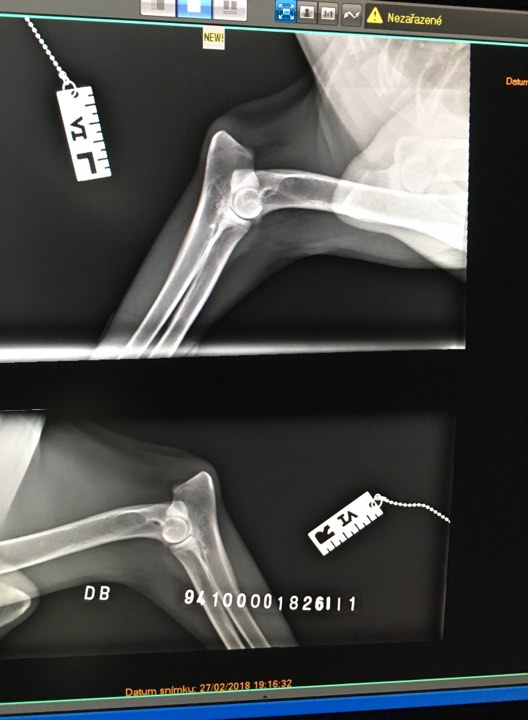

X-ray of HD is HERE, X-ray of ED is HERE